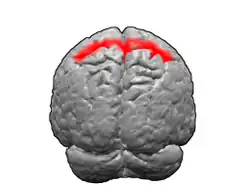

Цитоархитектоническое поле Бродмана 5

Цитоархитектоническое поле Бродмана 5 — область коры больших полушарий головного мозга, которая располагается в верхней теменной дольке позади постцентральной извилины. Является вторичной соматосенсорной зоной. При поражении у человека возникает астереогноз.

В 1909 году немецкий невролог Корбиниан Бродманн опубликовал[1] карты цитоархитектонических полей коры больших полушарий головного мозга. 5-е поле располагается в области верхней теменной дольки, позади постцентральной извилины.